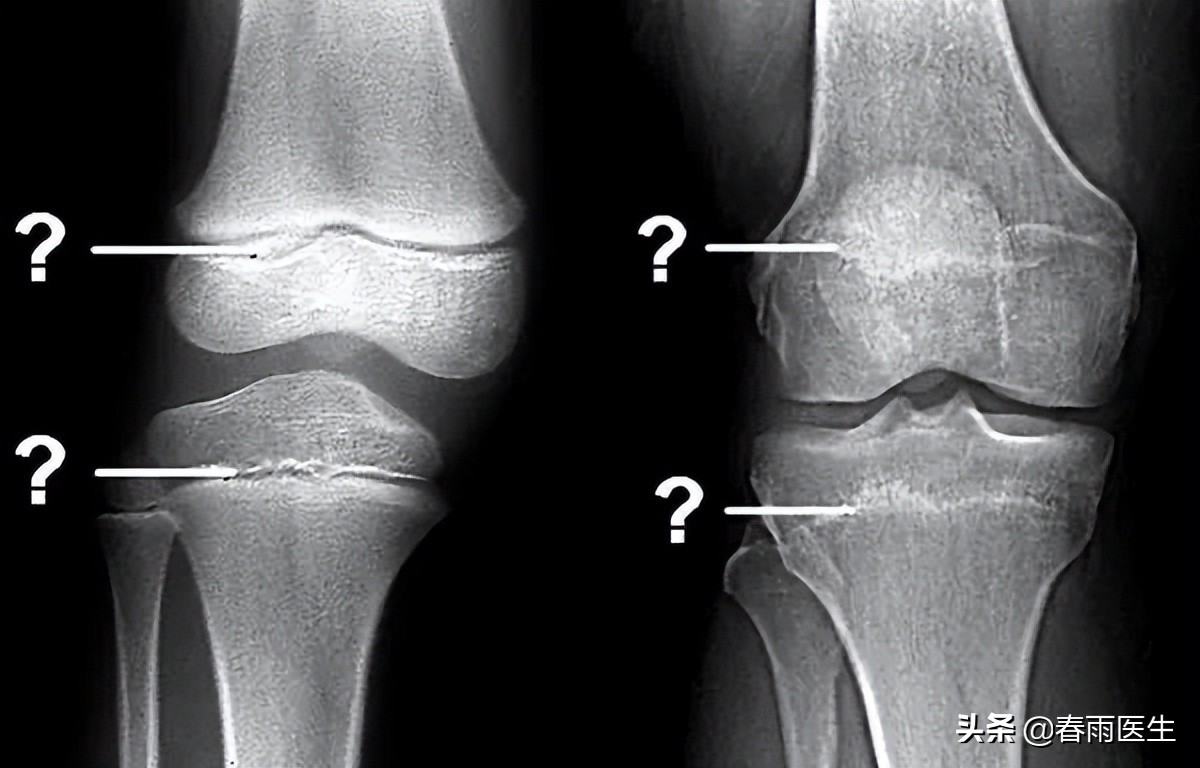

所以成年并不是长高的决定性因素,骨骺才是。那么,如何知道自己的骨骺有没有闭合呢?很简单,去医院拍个片就一目了然了。

(左为未闭合,右为已闭合/图源网络,侵删)

如果骨骺已经闭合了,就不要想着为了增高而去打个激素、吃个药、跑个步、跳个高、断个骨 (而且断骨增高手术风险非常大,我国卫生部规定:肢体延长术是一项骨科临床治疗技术,适应症为先天畸形、外伤、肿瘤、感染等原因所致的骨缺损或肢体不等长,以及因疾病引起的肢体畸形,严禁用于美容项目)......